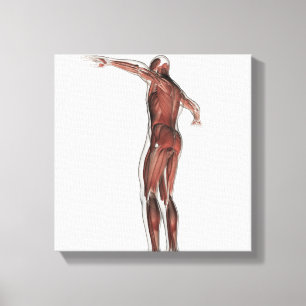

Lienzo Ilustracion médico del sistema muscular masculino

Precio 187,00 €